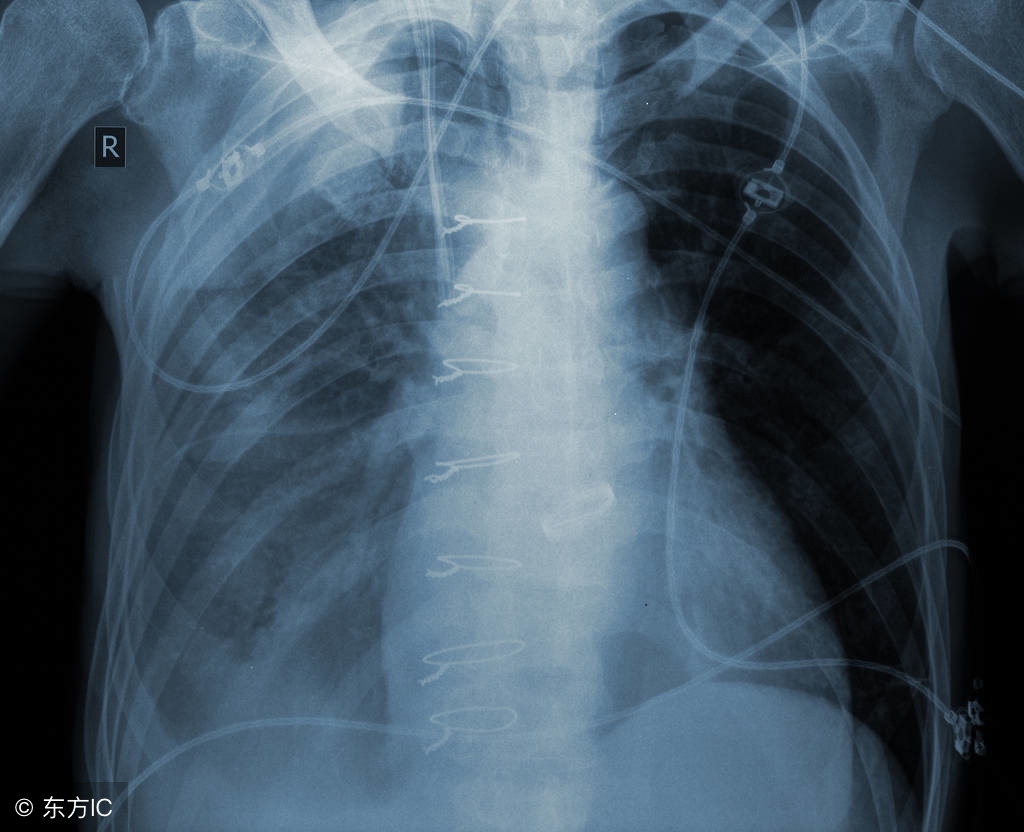

放疗或化疗的同时,往往给机体带来不良影响。其中最主要的就是白细胞下降严重时,甚至不得不中断治疗,直接影响治疗效果。